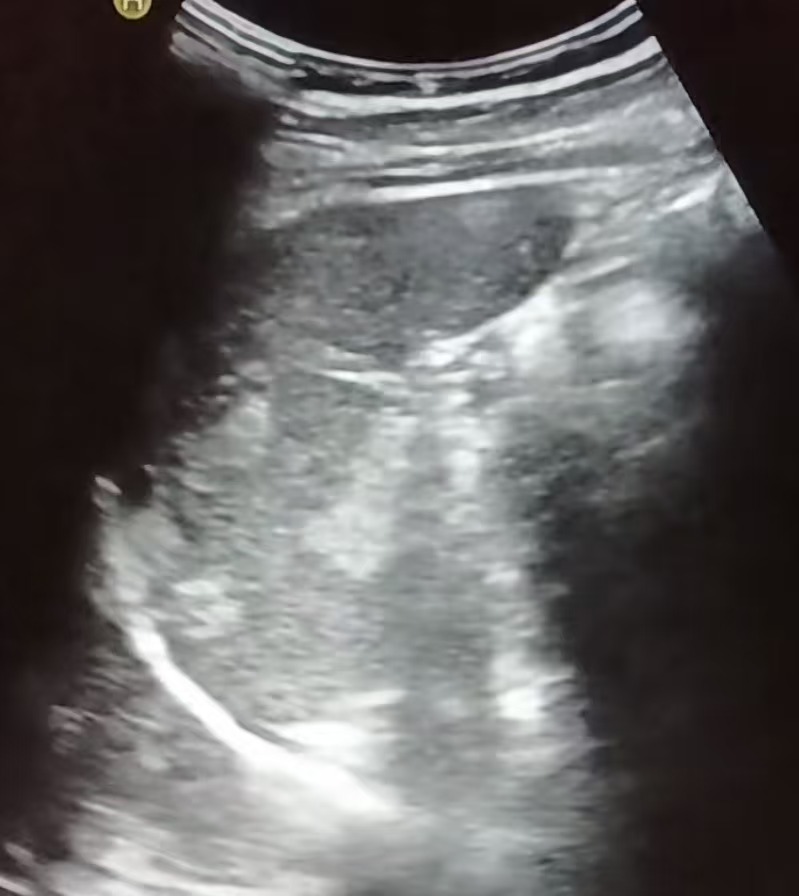

脾血管瘤的“超声肖像”:

常见类型与表现

脾血管瘤在超声下的“长相”并非千篇一律,主要可分为三种经典类型,超声医生正是通过这些特征来进行判断:

• 超声描述:脾实质内出现一个或多个边界清晰的明亮团块(回声高于周围正常的脾组织),像夜空中的星星。

• 内部特征:内部回声均匀或呈细网格状,后方回声无明显变化或略有增强。

• 血流信号:彩色多普勒超声下,多数未见明显血流信号或仅见周边点状血流。这是因为血管瘤内血流速度极其缓慢。

• 这是最典型、最经典的脾血管瘤表现,诊断信心较高。

• 超声描述:肿块呈灰暗(低回声)或明暗不均(混合回声)。

• 内部特征:边界可能依然清晰,但内部结构看起来不那么均匀。

• 血流信号:内部可能探测到较丰富的血流信号。

• 这类表现不典型,容易与其他脾脏病变(如淋巴瘤、转移瘤、错构瘤等)混淆。此时,超声医生的经验至关重要,常会建议进一步检查。

• 超声描述:肿块内同时包含无回声的液性区(囊性部分)和实性回声区。

• 形成原因:可能由于血管瘤内部出血、液化或血栓形成所致。

• 需要与脾囊肿、脓肿或坏死性肿瘤鉴别。